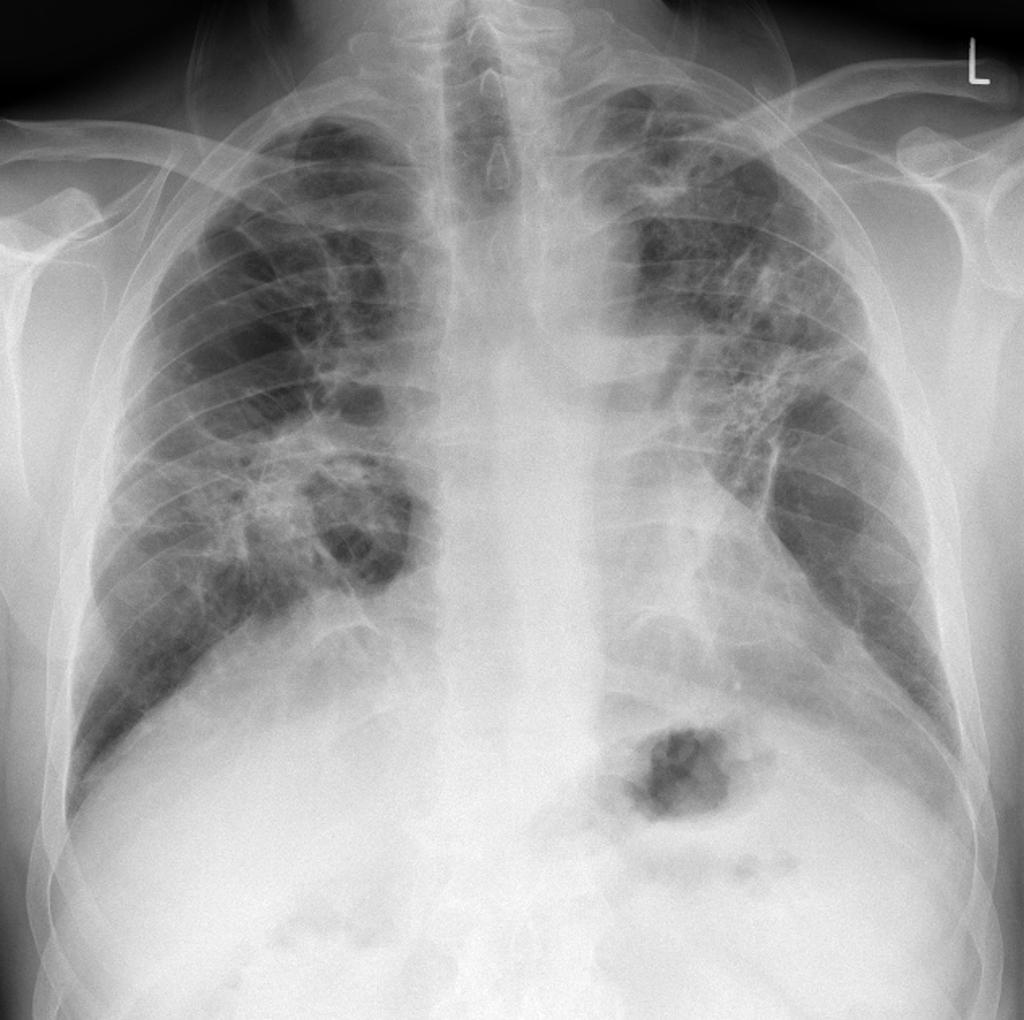

_右肺纖維化真實案例胸片

_中期肺纖維化X光